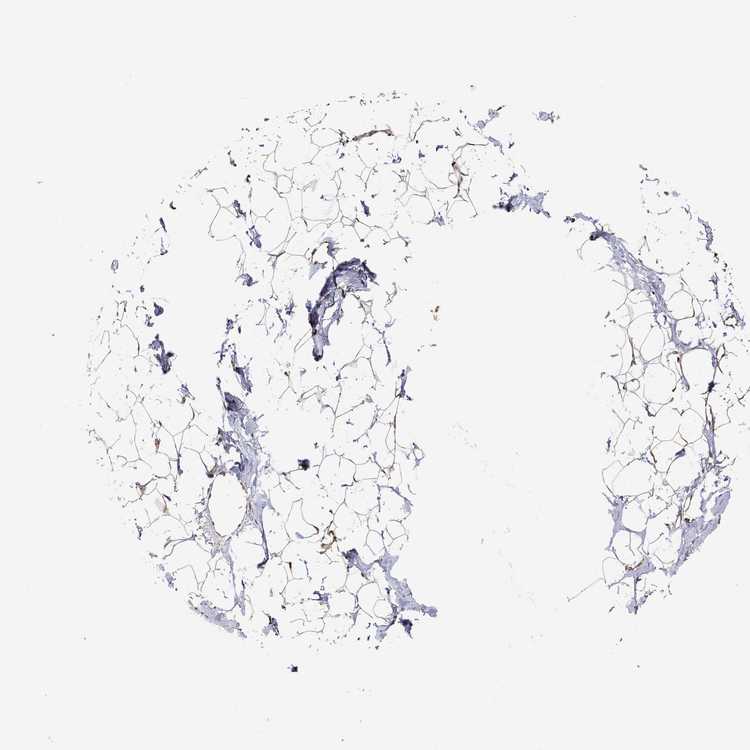

BREAST - Antibody stainingi

Antibody staining in the annotated cell types in the current human tissue is reported as not detected, low, medium, or high, based on conventional immunohistochemistry profiling in selected tissues. This score is based on the combination of the staining intensity and fraction of stained cells.

Each image is clickable and will lead to virtual microscopy that enables deeper exploration of all samples and also displays staining intensity scores, fraction scores and subcellular localization as well as patient and tissue information for each sample.

Antibody HPA069107

Adipocytes Medium

Glandular cells Medium

Myoepithelial cells High